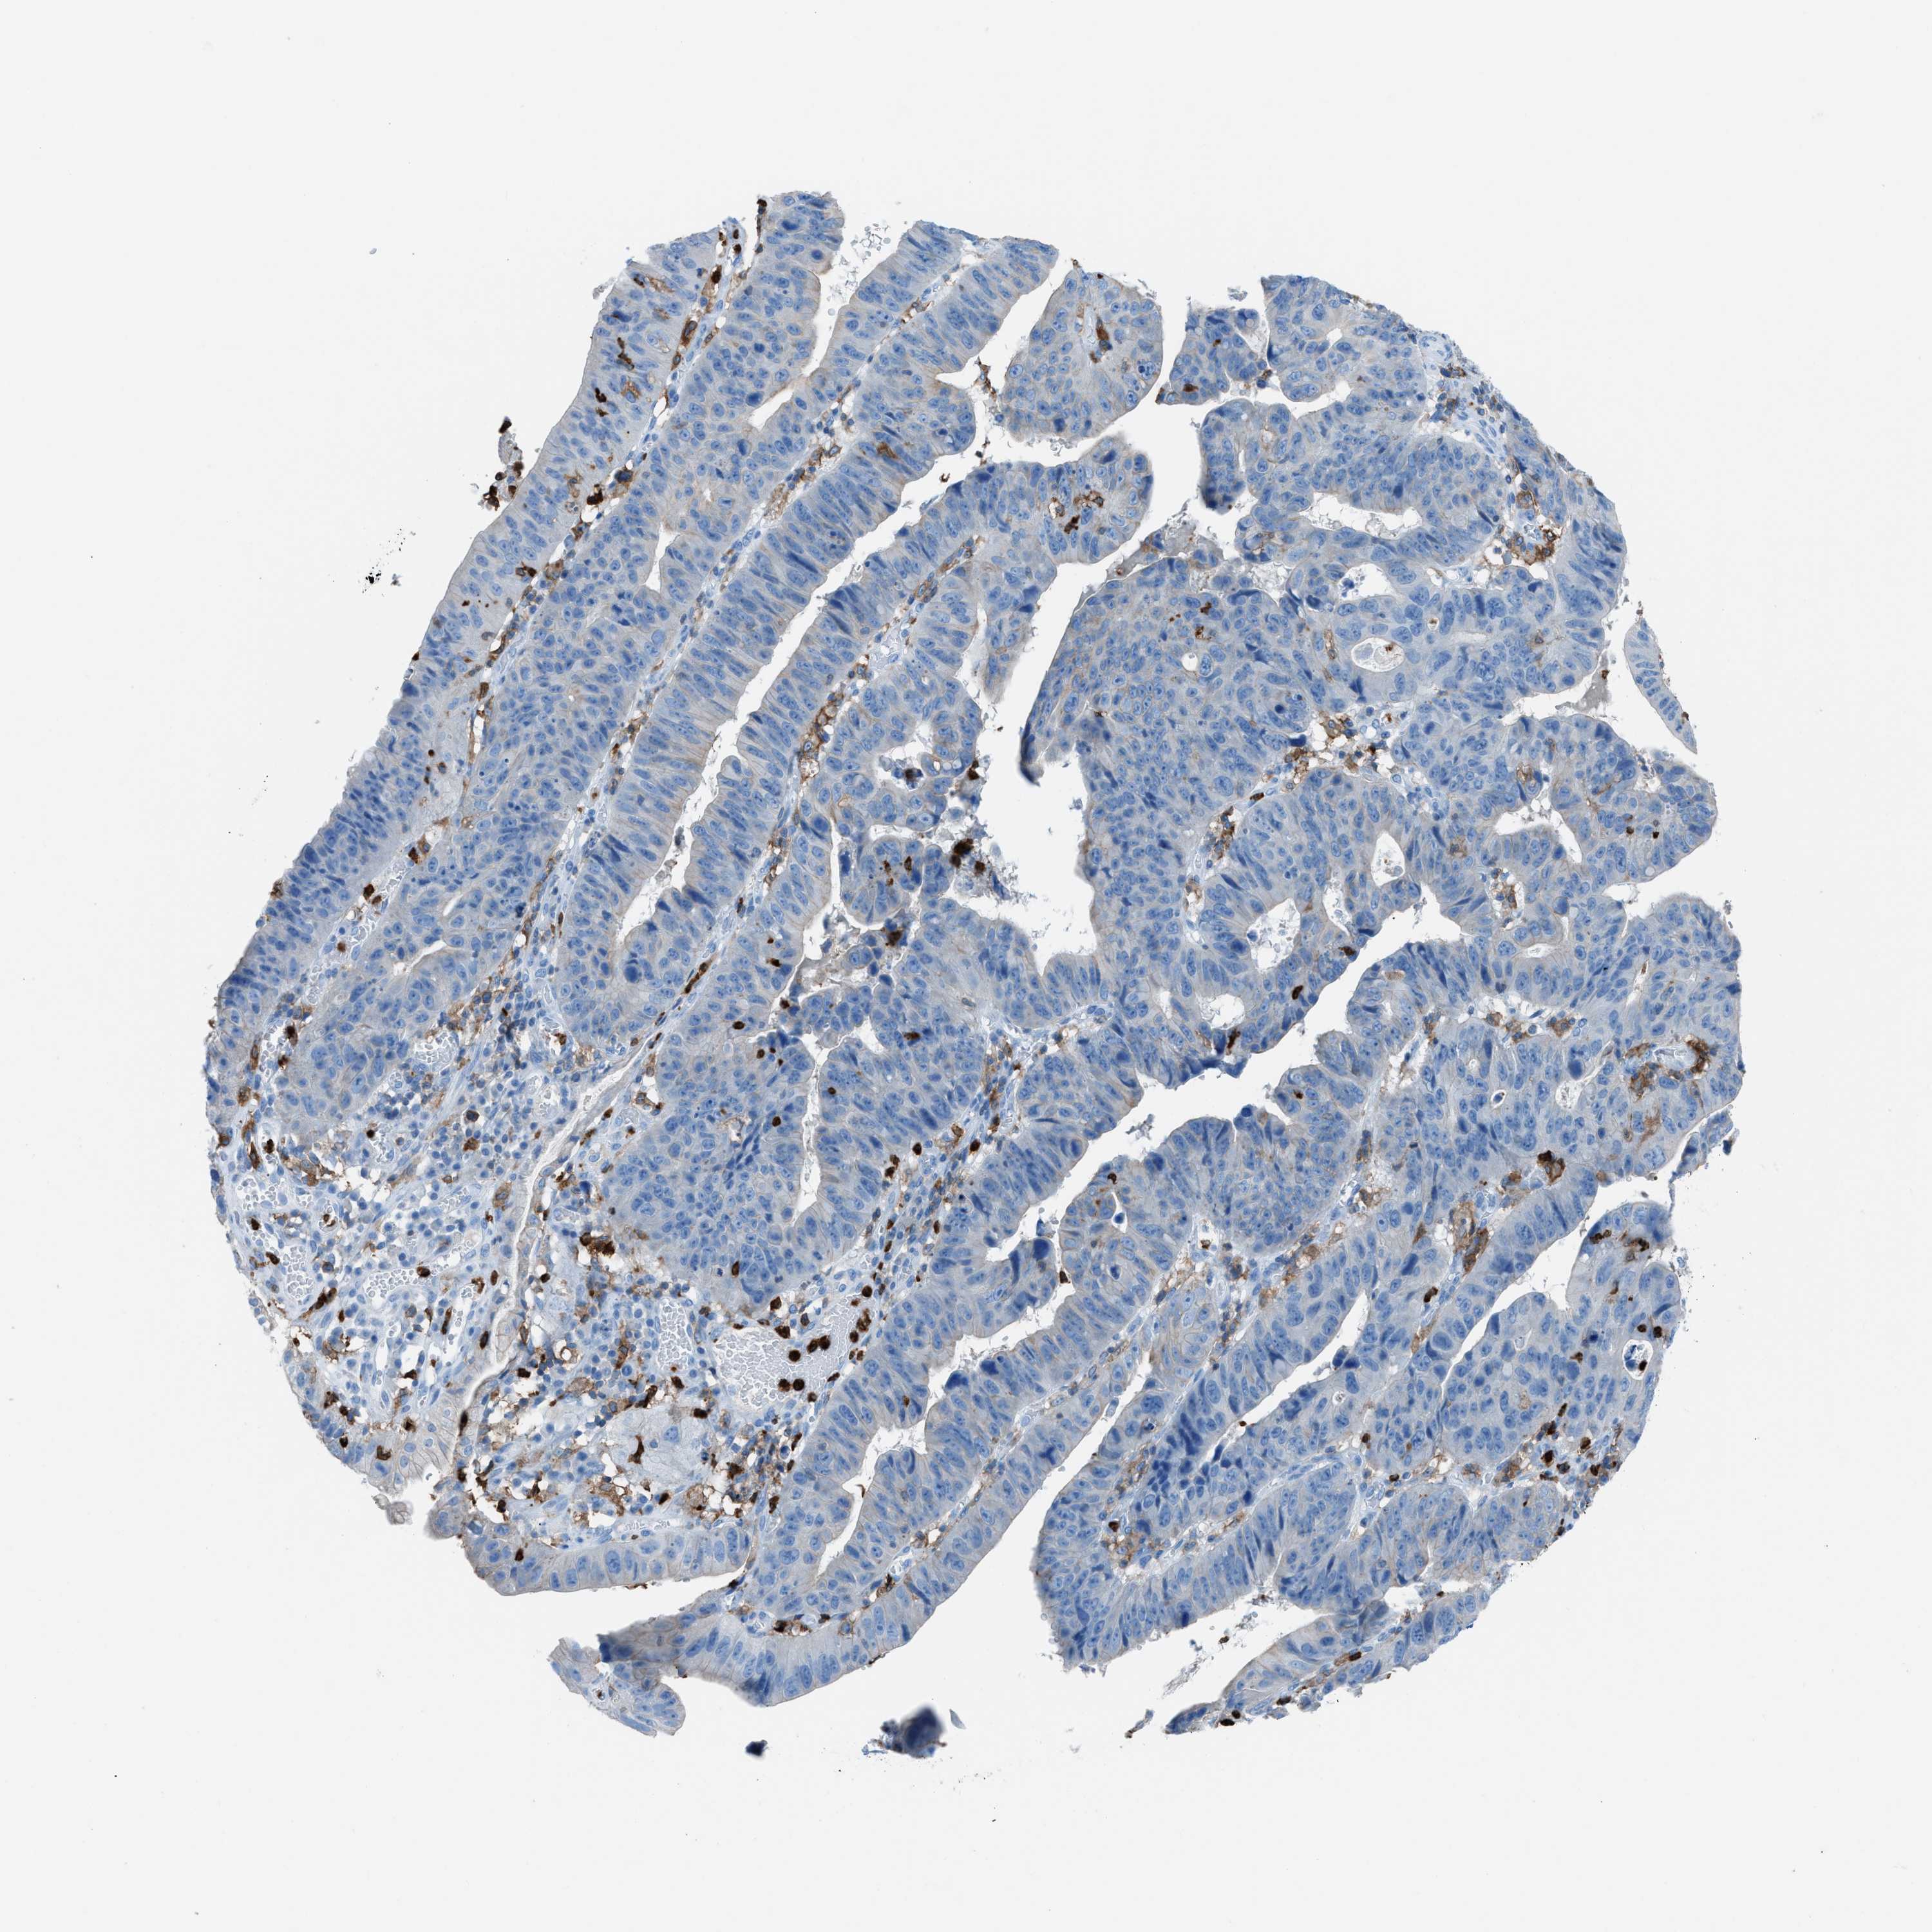

STOMACH CANCER - Protein expressioni

A mouse-over function shows sample information and annotation data. Click on an image to view it in a full screen mode. Samples can be filtered based on level of antibody staining by selecting one or several of the following categories: high, medium, low and not detected. The assay and annotation is described here.

Note that samples used for immunohistochemistry by the Human Protein Atlas do not correspond to samples in the TCGA dataset.

Antibody stainingi

Antibody staining in the annotated cell types in the current human tissue is reported as not detected, low, medium, or high, based on conventional immunohistochemistry profiling in selected tissues. This score is based on the combination of the staining intensity and fraction of stained cells.

Each image is clickable and will lead to virtual microscopy that enables deeper exploration of all samples and also displays staining intensity scores, fraction scores and subcellular localization as well as patient and tissue information for each sample.

Antibody HPA008877

Antibody HPA016894

Staining

High

Medium

Low

Not detected

Intensity

Strong

Moderate

Weak

Negative

Quantity

>75%

75%-25%

<25%

None

Location

Nuclear

Cytoplasmic/membranous

Cytoplasmic/membranous,nuclear

Adenocarcinoma, NOS